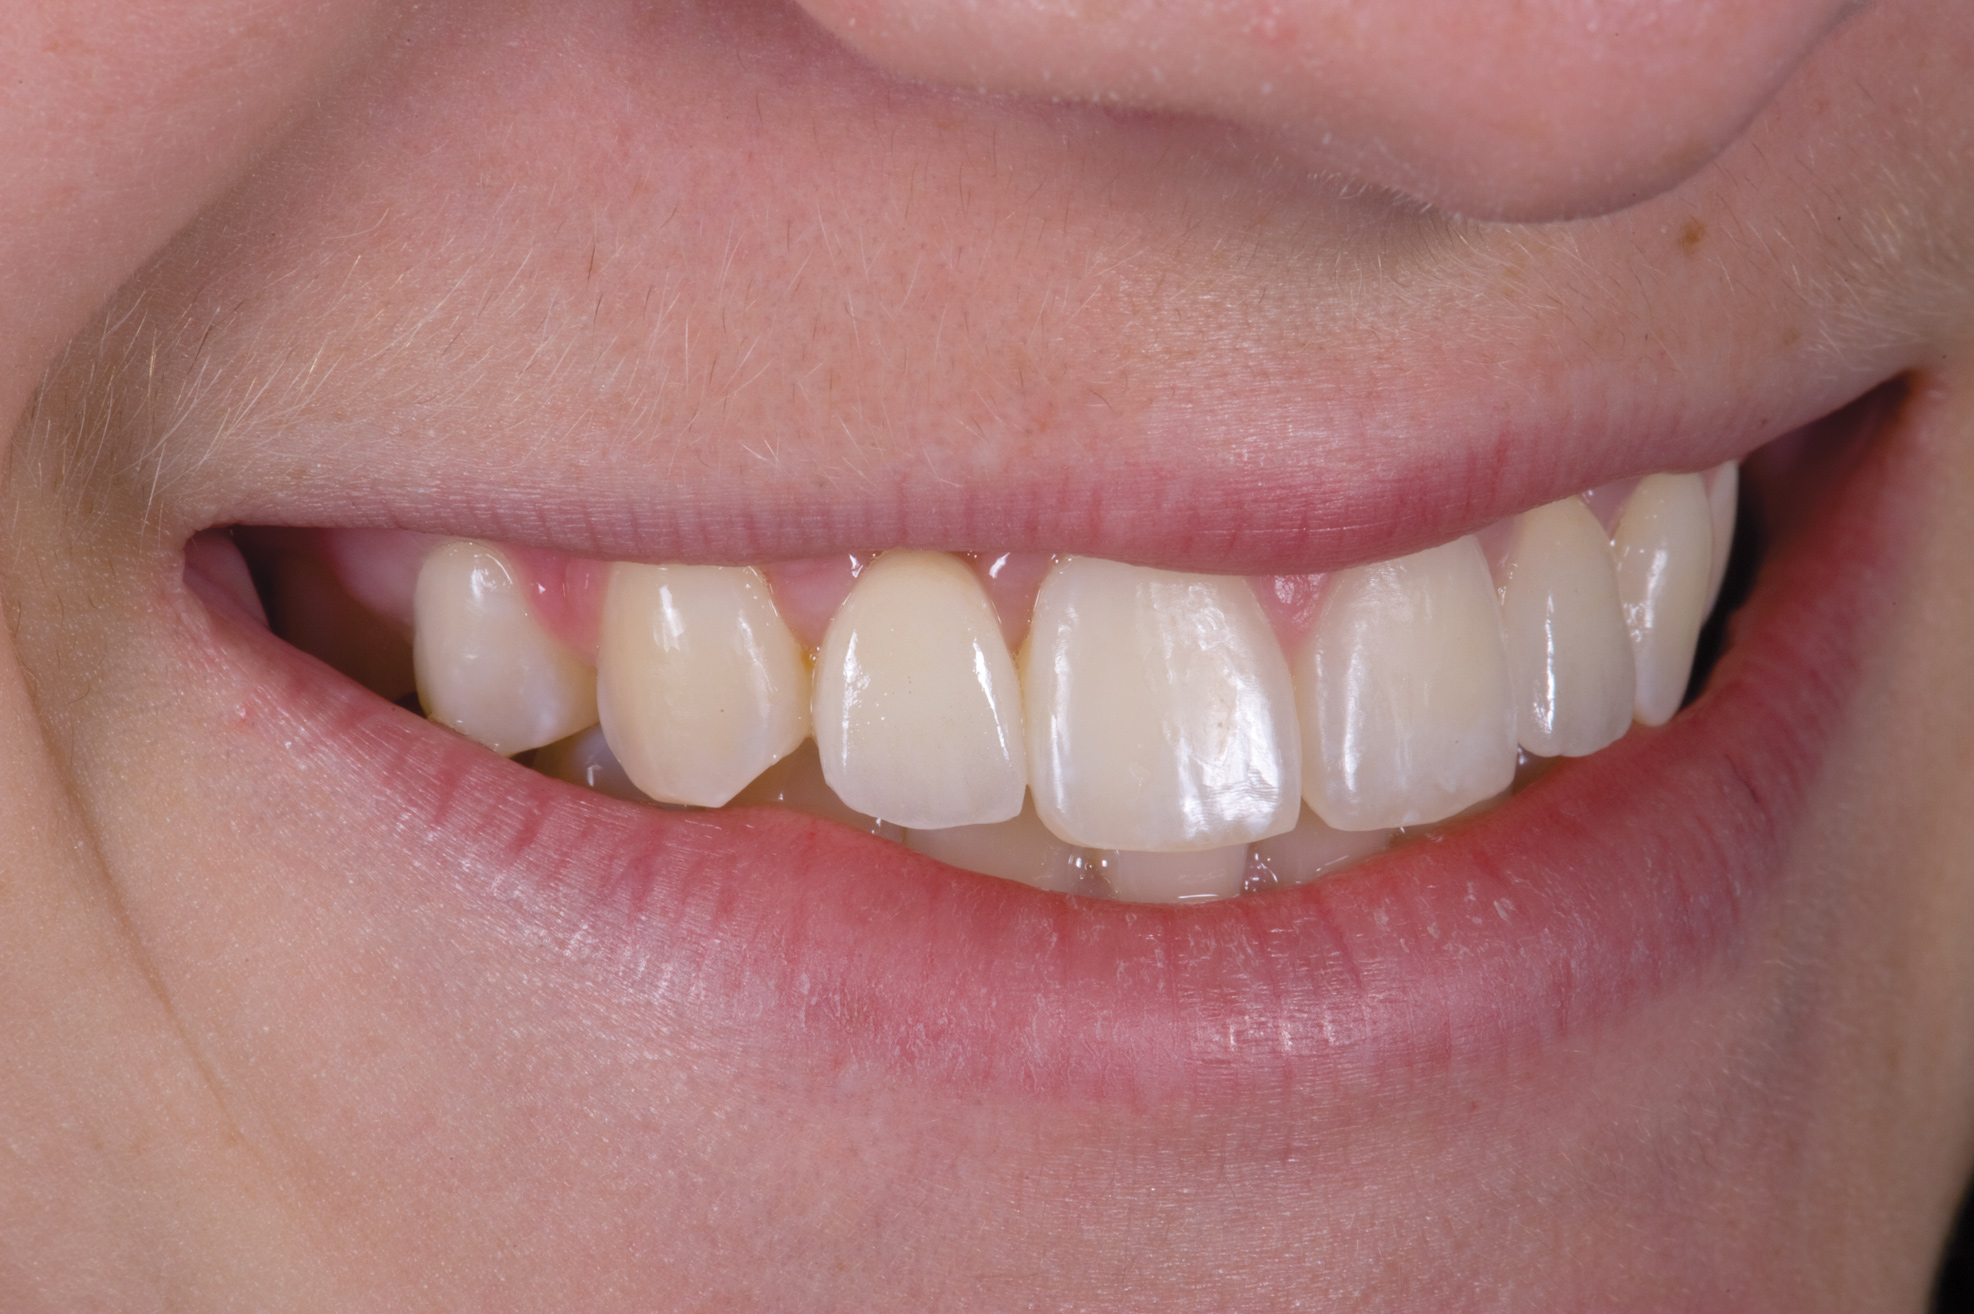

Case Presentation 2: Patient Does Not Want to Have an Implant Placed

Some patients do not want an implant due to the need for surgical intervention, and others may not have enough space for implant placement. A 15-year-old patient presented to the office after completion of orthodontic treatment to idealize the spacing of her teeth and improve her occlusal relationship (Figure 12 through Figure 14). Because both of her maxillary lateral incisors were missing, the patient was wearing a retainer with lateral incisor pontics. She had a busy school schedule, but expressed her desire for a fixed restorative option. All of her options were discussed, and the patient was informed that if she wanted an implant, she would have to wait for at least 3 to 4 years for completion of growth. The patient was not sure if or when she wanted to have an implant placed in the future, especially considering her busy schedule and desire to attend college after high school. Considering her age and the need to be conservative, a single-wing zirconia Maryland Bridge was chosen as the ideal prosthetic replacement option. Because bonding a non-etchable and smooth surface such as zirconia requires chemical adhesion, it was decided to use a modified technique to make the bridge more retentive. One of the ways to improve adhesion of a zirconia bridge is to use an etchable feldspathic ceramic layer on the internal surface of the zirconia retainer.56-58 Unfortunately, it can be difficult to determine the thickness of the ceramic and ensure accurate seating of the restoration.

Fig 12. 15-year-old girl after orthodontic therapy idealized maxillary lateral incisor spaces.

Figure 12

Fig 13. Deficient ridges in the areas of the missing lateral incisors.

Figure 13